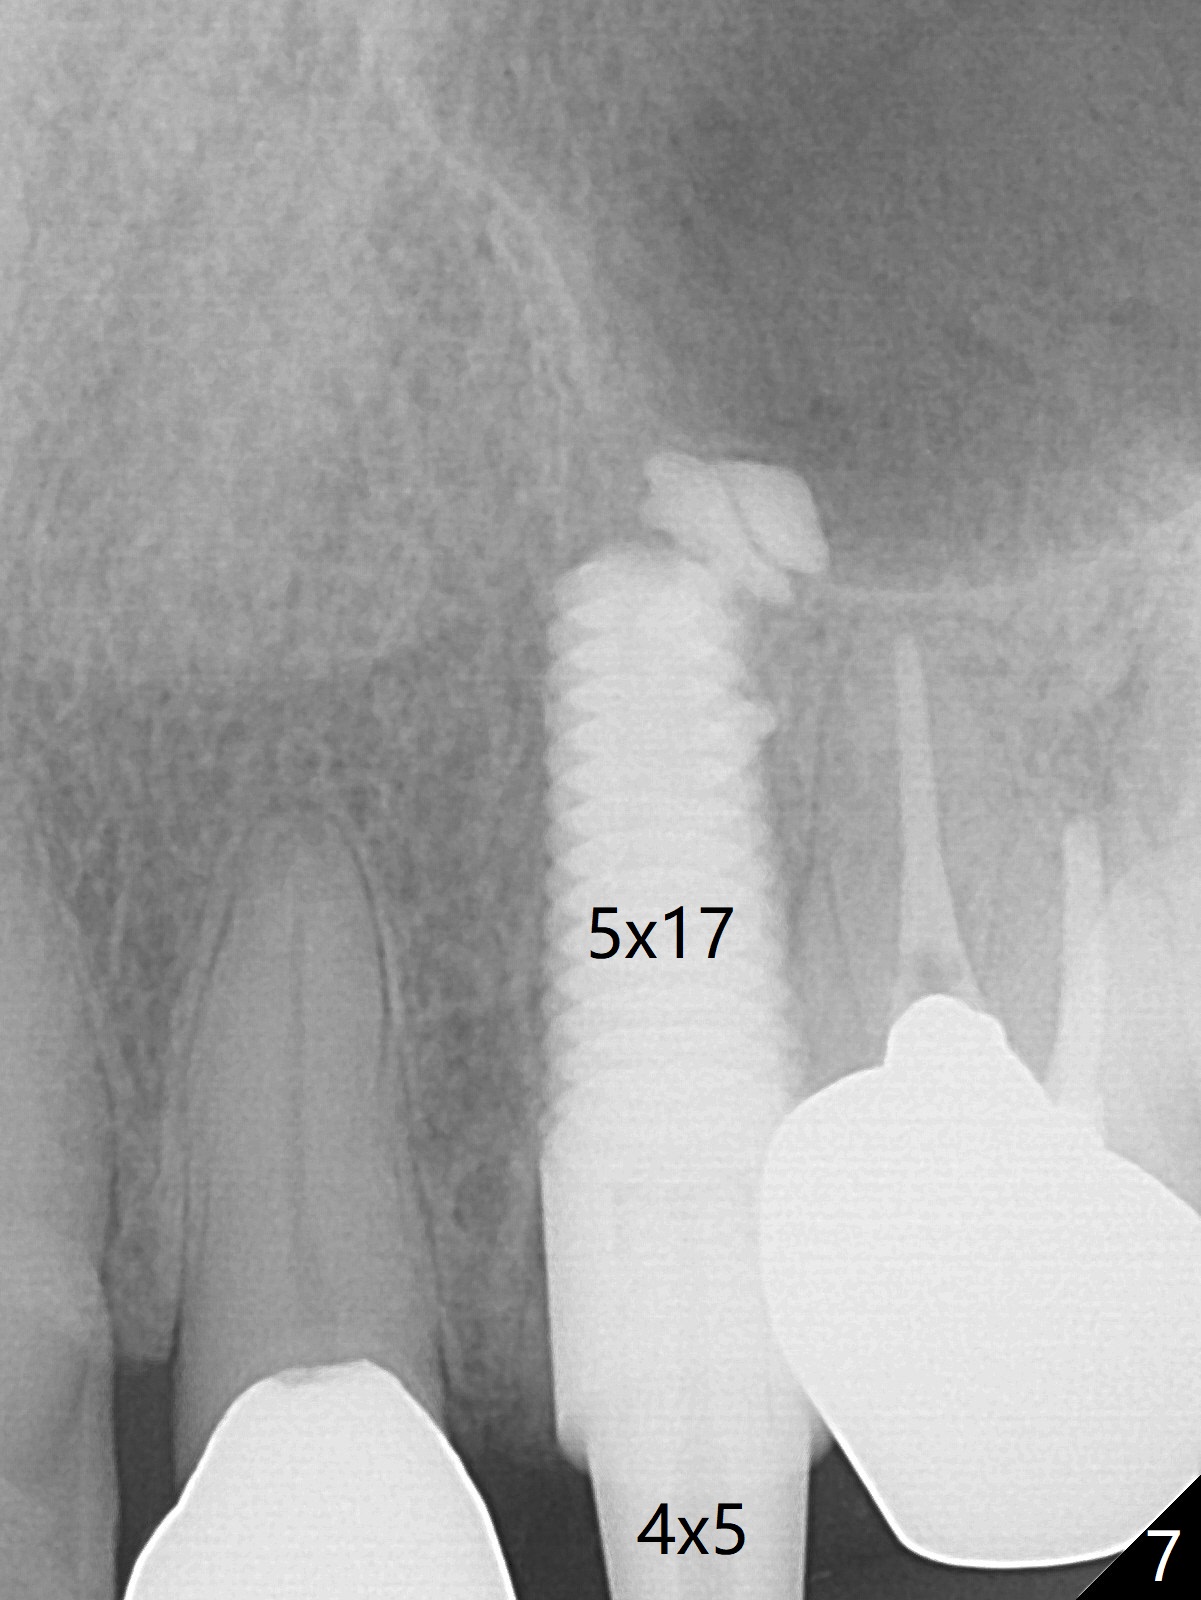

Extraction of the residual root at #11 (Fig.1) turns out to be difficult (Fig.2 (arrow: after use of small elevator). The tooth is sectioned (Fig.2 *); the palatal portion is removed, while the buccal one is trimmed until new moon-shaped and subgingival (Fig.3 * (gauze (G) packed in the socket while photo taking)). Initial osteotomy is 20 mm deep with nasal floor perforation (Fig.4). The subsequent depth is 17 mm (Fig.5). When a 5x17 mm tissue-level implant is placed (Fig.6,7; >60 Ncm), there is a gap between it and the socket shield (Fig.6 *). Gap-filling Vera Graft (Fig.8 *) also covers the shield prior to fabrication of an immediate provisional (Fig.9). There is no apparent bone loss 3.5 months postop (Fig.10). There is no buccal plate resorption 9 months postop (Fig.11). The implant is doing well 2 years postop (1 year 9 months post cementation, Fig.12).